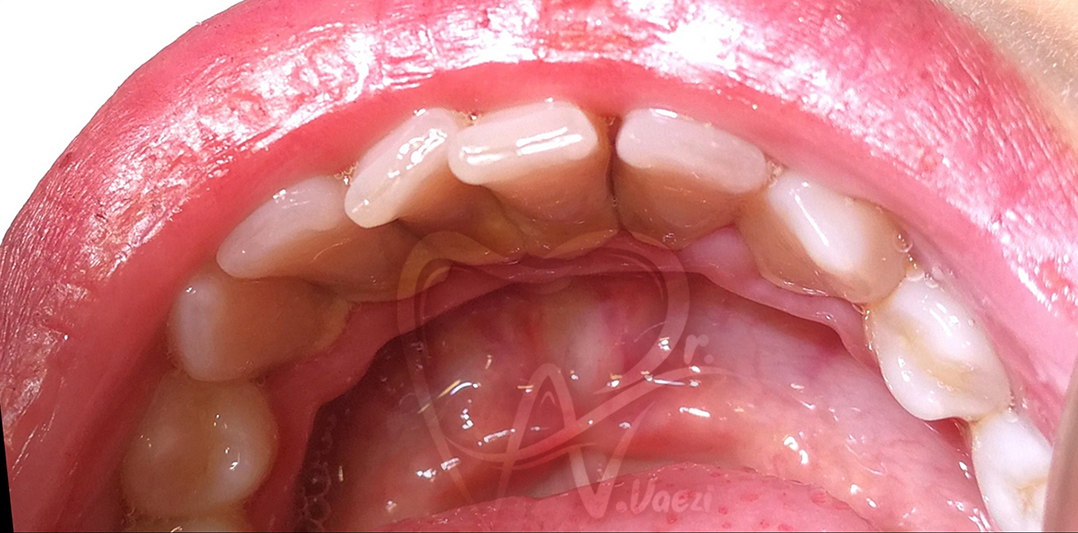

2- جرم گیری فک پایین

بعد از جرم گیری

قبل از جرم گیری